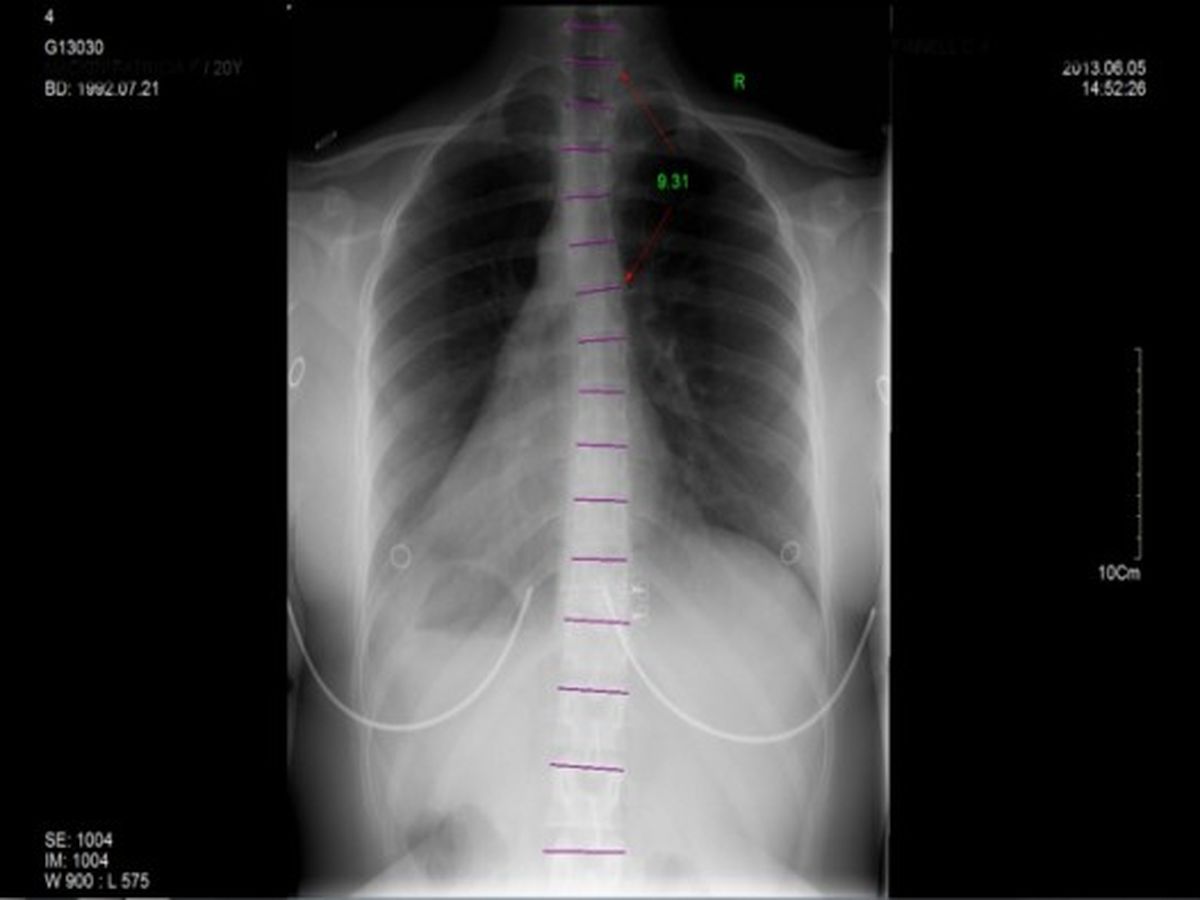

Below you see the x ray images I received back showing the damage.

Recently after finally getting my chance to go see a chiropractor and get some X rays done was when I realized how bad the damage was. The news I got back was that I'm doing pretty badly, which for someone who needs to sew to make a livelihood is a terrible thing to find out.

I knew it was bad from simply not being able to function without pain everyday, but these X rays really made it real for me. I was told very honestly that I don't have a lot of time before this gets more critical than it already is, and frankly I can barely get through the day anymore without searing pain in my back, to the point of maybe not being able to finish school.

The prognosis is that if I wait longer, the bones have a risk of fusing together in the wrong position, and causing much more serious heath issues that threaten to do a lot worse than just cause me pain.